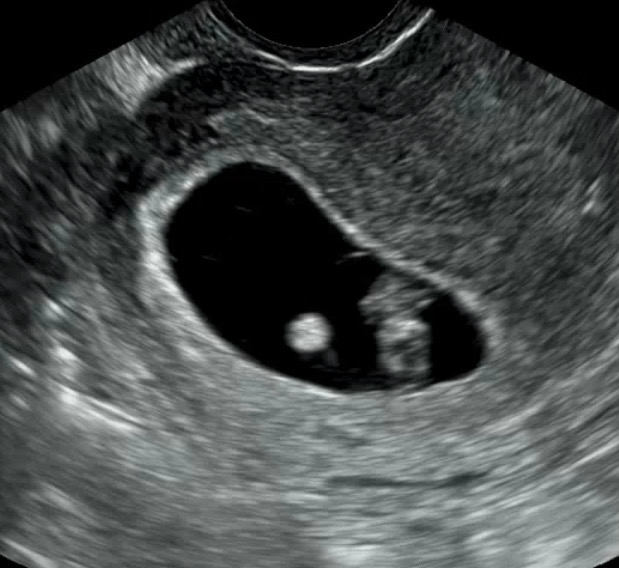

다들 젤리곰 하시는데 요게 젤리곰 맞나요?

저는 왜 잘 안보이는거같죵?ㅠㅠ 앞모습인지 옆모습인징… 흐리흐리해요ㅠㅠ

한 달 뒤면 사람 태가 날거에용 ㅠㅠ 젤리곰은 보통 8주 후반~ 9주 정도 같아요 아기 크기마다 다르지만 ㅎㅎ

몇주세요!!?? 조금더 컸을때가 더 젤리곰 같을거 같아요-!

8주에용 ㅜㅜ 이제 한당 뒤에 오라던데 그럼 젤리곰 못보나용 ㅜㅜ